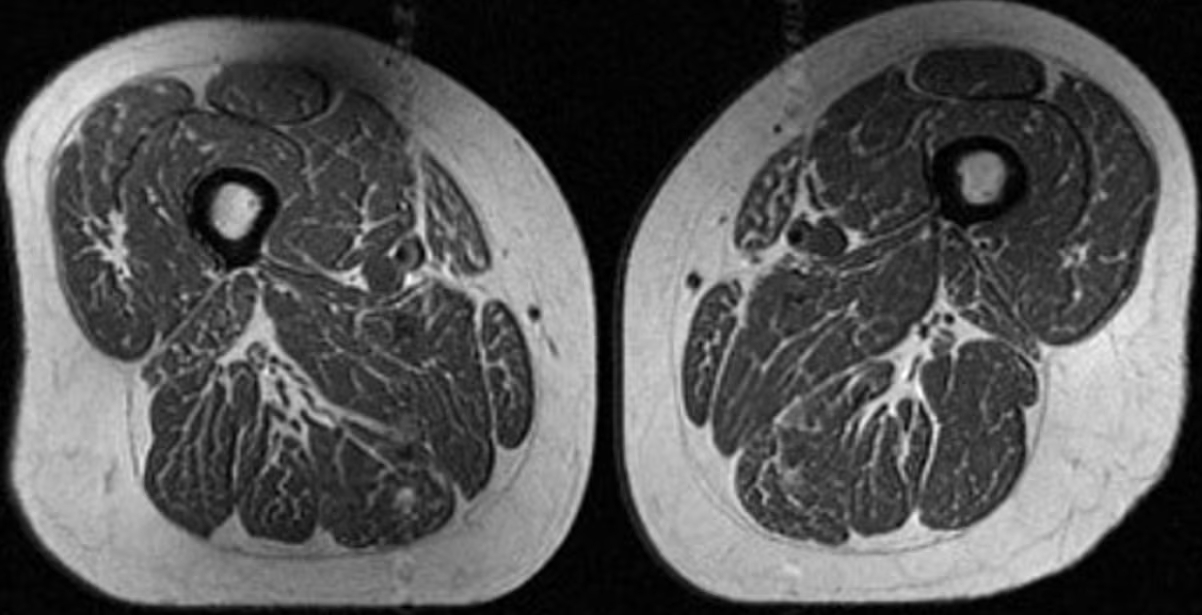

Η εικόνα που εξετάζουν οι ερευνητές δεν είναι ωστόσο φαγητό. Πρόκειται για μαγνητική τομογραφία (MRI) του μηρού μιας 62χρονης γυναίκας, η οποία αντλούσε το 87% των ετήσιων θερμίδων της από υπερεπεξεργασμένα τρόφιμα.

Στη μελέτη, μια δεύτερη γυναίκα 61 ετών εμφάνισε επίσης λιπώδη διήθηση στους μηρούς, αλλά σε μικρότερο βαθμό, με το 29% της διατροφής της να προέρχεται από υπερεπεξεργασμένα τρόφιμα.

Η γυναίκα με 87,1% υπερεπεξεργασμένα τρόφιμα στη διατροφή της (A στην εικόνα παρακάτω) είχε BMI 32,6 και χαμηλότερη φυσική δραστηριότητα από τη δεύτερη γυναίκα (B στην εικόνα), η οποία είχε BMI 31,8 και 29,5% υπερεπεξεργασμένα τρόφιμα. Παρ’ όλα αυτά, η πρώτη εμφάνιζε πολύ πιο έντονη λιπώδη διήθηση στους μηρούς.